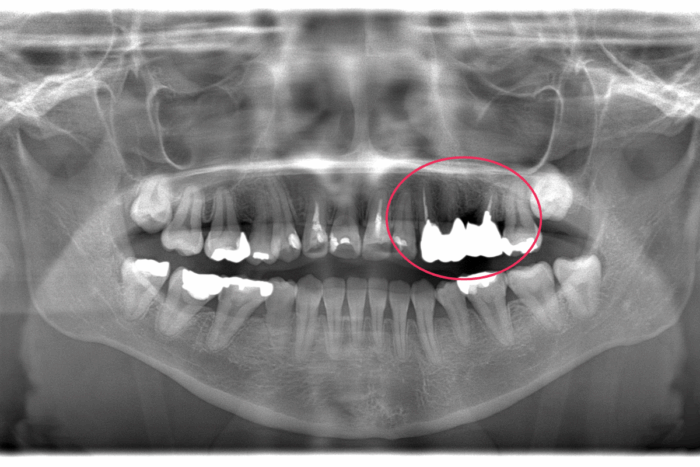

患者さま:30代女性/左上4・5・6番にメタルブリッジ

主訴:歯のガタつき・かみ合わせが反対

矯正治療のために上下左右4本抜歯する必要がありました。そのため、抜歯する歯のうち1本は、ブリッジを分割しポンティック部分(ブリッジの真ん中の人工歯のこと)を除去して代用しました。ワイヤー矯正で歯並びとかみ合わせを改善しました。

- 診断名:叢生・反対咬合

- 抜歯部位:上顎右側第二小臼歯、下顎右側第二小臼歯、下顎左側第一小臼歯